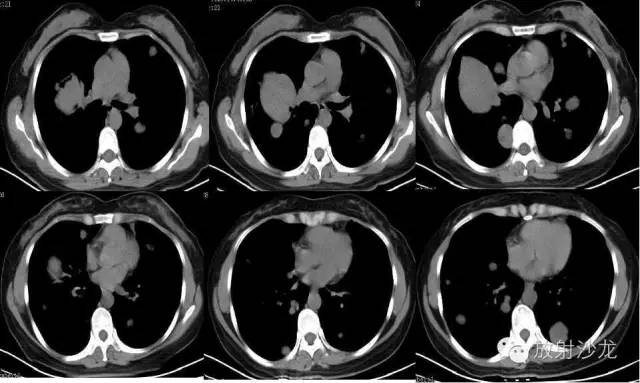

【影像表现】

双侧胸廓对称,纵隔居中。双肺可见散在多发大小不等类圆形软组织密度影,密度欠均,边界较清,最大者约5.32cm*7.88cm*6.75cm,右肺中叶、下叶可见一不规则形透亮影,内无肺纹理,纵隔未见明显肿大淋巴结,胸膜无增厚,右侧胸腔内可见弧形液体密度影。

【诊断结果】

双肺多发结节占位病变

右肺中下叶肺大泡

右侧胸腔积液